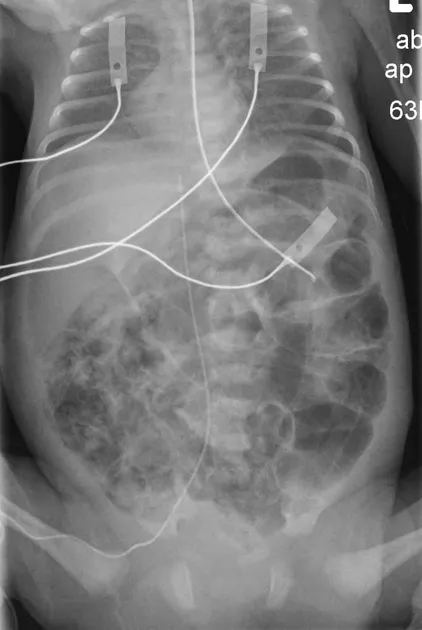

- Gas-producing organisms invade the bowel wall, causing the hallmark finding of pneumatosis intestinalis.

- Imaging (Serial AXRs): Key to staging (Modified Bell's Staging).

- Stage I (Suspected): Normal or mild ileus.

- Stage II (Definite): Pneumatosis intestinalis (pathognomonic) or portal venous gas.

- Stage III (Advanced): Pneumoperitoneum (perforation).